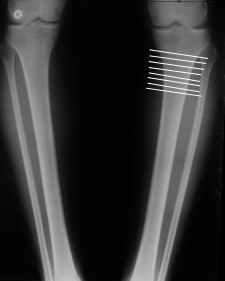

Или давай для простоты я картинку с несколькими вариантами прилагаю, которая линия, если считать сверху, тут оптимальна с высоты твоего немалого опыта? И имеет ли значение, как сечь - параллельно суставной щели, перепендикулярно диафизу или иначе как-то?

Нет, про вырубание и речи нет. Это про линию остеотомии. Chris Wilson вот советует делать косо, начать медиально см в 12 от суставной щели и направление на головку малоберцовой кости.

Хочется одномоментно сделать, и фиксировать не аппаратом. Поэтому чем дистальнее - тем удобнее. Так вот насколько дистально можно? И для исправления оси, чем дистальнее, тем больше надо латерально смещать периферический отломок для сохранения оси.